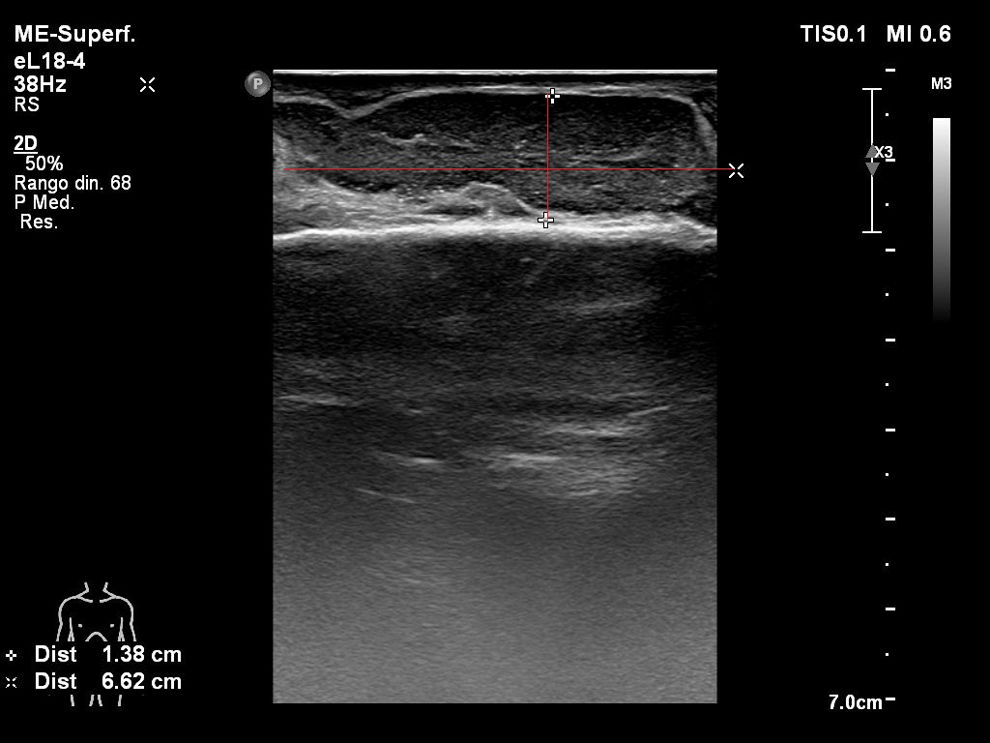

Trasladada a la unidad de cuidados intensivos, se inicia antibioterapia intravenosa de amplio espectro (meropenem+amikacina+linezolid) previa toma de hemocultivos; al objetivar como posible foco infeccioso tenosinovitis séptica en la mano derecha, se modifica por meropenem con daptomicina intravenosa y se solicita interconsulta a traumatología para valoración y realización de ecografía de partes blandas (fig. 2). Se realiza drenaje con limpieza por traumatología en la propia unidad de cuidados intensivos, con incisión en el dorso de la mano, drenaje de abundante débito hemopurulento, toma de muestras para estudio microbiológico, limpieza con agua oxigenada y povidona yodada, y mantenimiento de drenaje tipo Penrose con curas diarias durante 5 días. Se objetiva aislamiento en hemocultivos y muestras de la herida de S. aureus sensible a meticilina (SASM), por lo que se desescala antibiótico a cloxacilina intravenosa. Presenta una mejoría progresiva de los síntomas y signos analíticos de shock séptico. Se consigue la estabilización de la paciente, por lo que se logra despertar, y se procede a la extubación al quinto día de ingreso en la unidad de cuidados intensivos. Los controles microbiológicos posteriores fueron negativos. Se realizó un ecocardiograma de control para descartar endocarditis infecciosa secundaria a bacteriemia por SASM. Se dio de alta a la planta de hospitalización convencional de traumatología con el diagnóstico de shock séptico secundario a tenosinovitis infecciosa en mano derecha por SASM.

Imagen ecográfica de la superficie dorsal de la mano derecha; se aprecia el tendón extensor común de los dedos, de espesor y ecoestructura normales, rodeado de material hipoecogénico, móvil, en un segmento de unos 6,62cm de longitud y 1,38cm de espesor, con hipervascularización de la sinovial.